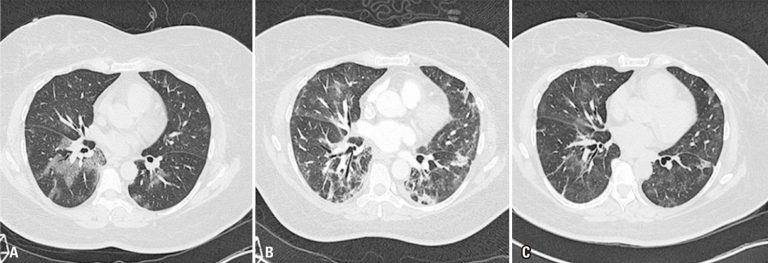

Temporal evolution of tomographic findings of pulmonary infection in COVID-19

We very enthusiastically read the excellent review article entitled “COVID-19 findings identified in chest computed tomography”, by Rosa et al.,() published in the last issue of this journal. This manuscript shows the relevance of chest computed tomography (CT) in detecting the pulmonary manifestations of the coronavirus disease 2019 (COVID-19), presenting cases in a very didactic manner, but not discussing its role in the follow-up of the disease. Although we know this was not the scope of the authors, we would like to complement this discussion with some topics related to the impact of this imaging method in the prognosis and progression (long-term follow-up) of COVID-19.